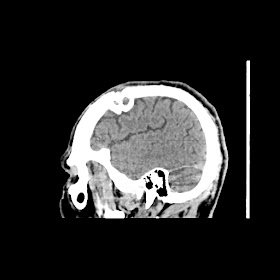

Radiologycal images :